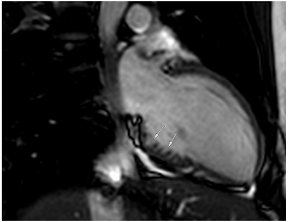

Figure 2.

Tissue characterization with Late Gadolinium Enhancement (LGE) and Extracellular Volume (ECV) Map. Adapted with permission from [33].

To avoid the low but important risks of endomyocardial biopsy, which can have an overall complication rate of up to 6% [2], myocardial fibrosis can be assessed non-invasively using CMR: LGE is suitable for detecting irreversible replacement fibrosis and myocardial scarring and T1/ECV mapping for detection of potentially reversible (reactive) interstitial and more diffuse fibrosis (not detectable by LGE) (Figure 2).

Myocytes account for approximately one-third of all cells in normal myocardium. The remaining two-thirds of cells include endothelial and vascular smooth muscle cells and fibroblasts in interstitial/perivascular spaces [2] (Figure 2). Normal CMR ECV values vary between 25.3 and 3.5% [43]. Ideally, age- and sex-corrected normal values for ECV should be used [44]. Hypertension affects both the cellular and extracellular compartments of the myocardium. In addition to cardiomyocyte hypertrophy, in HHD, fibrous tissue (primarily type I fibrillar collagen) is deposited in the extracellular matrix over time and leads to increased tissue stiffness (i.e., diastolic dysfunction) [2]. ECV values are higher in hypertensive patients with LVH than in patients without LVH, and eccentric forms of hypertrophy seem to have the most fibrosis and highest ECV values, together with more pronounced systolic impairment and are associated with a poor cardiovascular prognosis (Figure 1) [2,6]. CMR-derived T1 mapping and strain analysis seem to be related, but an adequate comparison of the performance of these parameters is often limited due to the lack of harmonization of measurement methods [35]. Furthermore, ECV values seem to correlate with many blood biomarkers associated with (i) systemic inflammation; (ii) metabolism; (iii) fibrosis; (iv) chemotaxis; and (v) platelet activation [6]. This may suggest that an increase in ECV in hypertensive patients is a (non-specific) imaging biomarker of inflammation, tissue remodelling, atherogenesis, or metabolic disorder in patients with HHD [6]. Given the clinical consequences of myocardial fibrosis in HHD and considering the potential for recovery of fibrosis with appropriate treatment, the need for an accurate diagnosis of myocardial fibrosis is apparent.